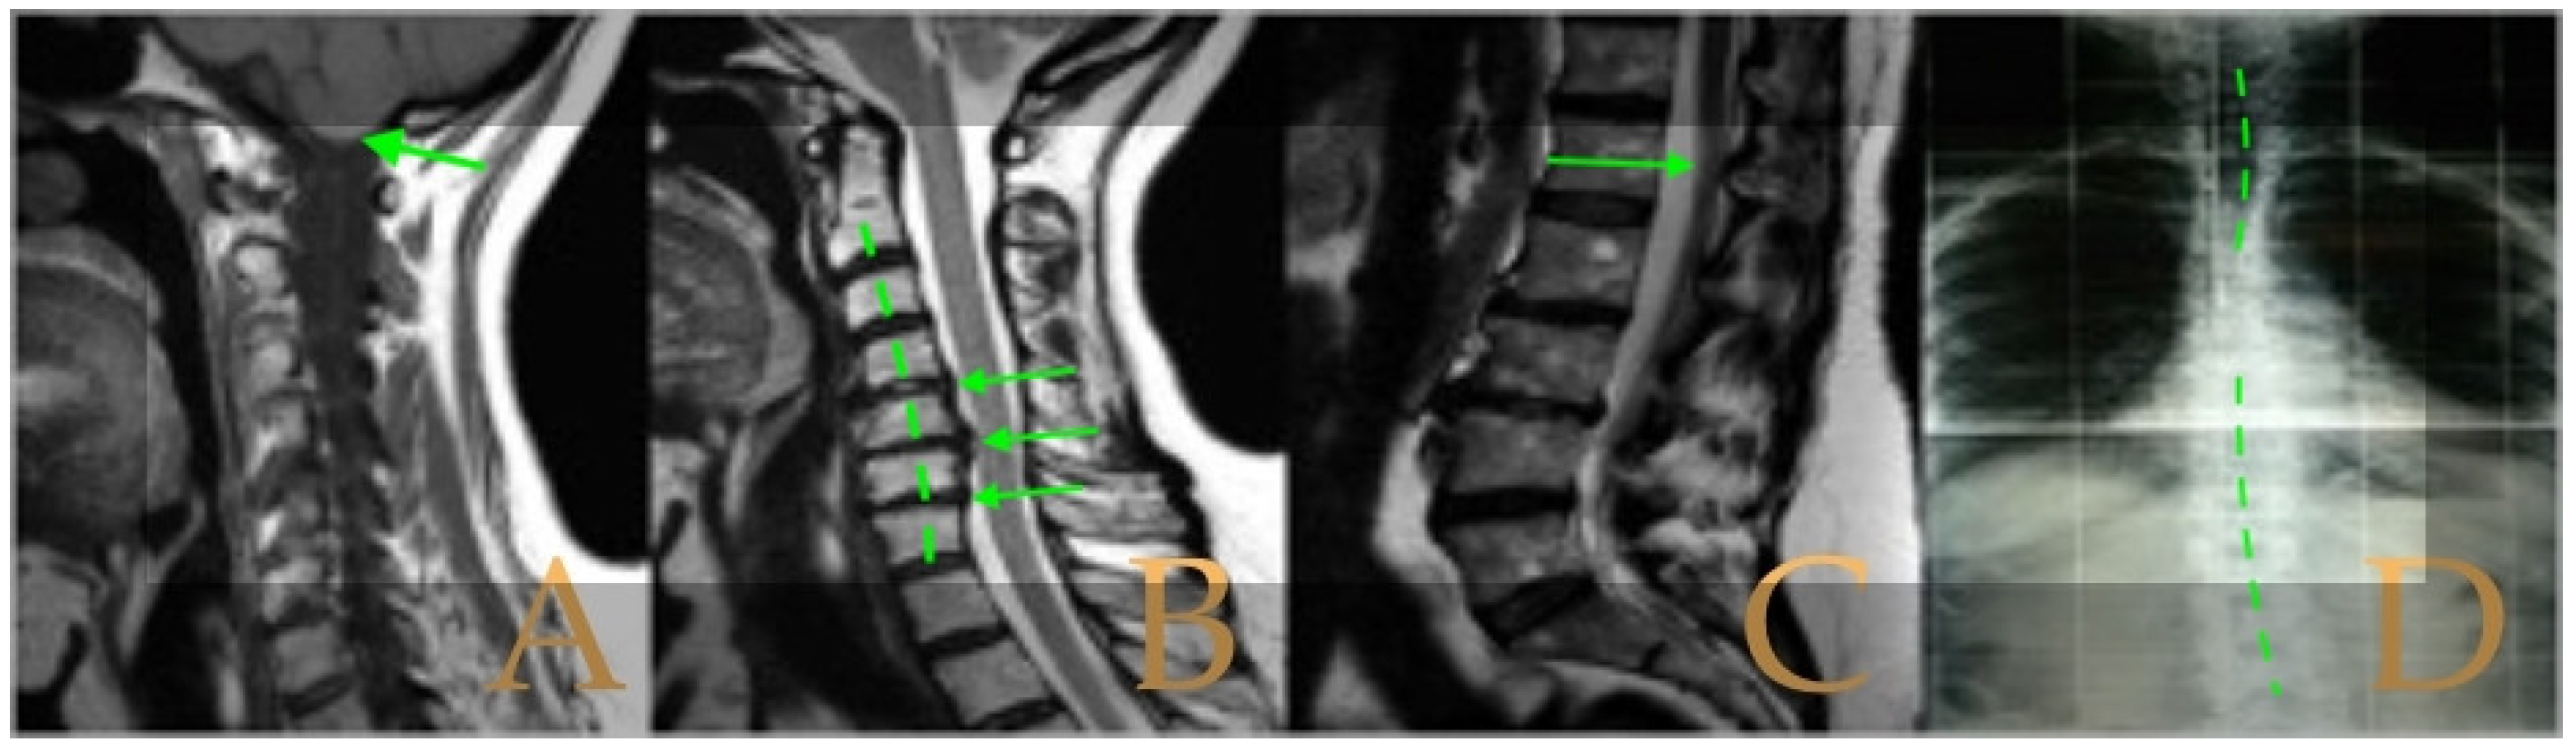

The cranio-vertebral magnetic resonance showed empty sella turcica, discrete descent of the cerebellar tonsils, C4-C5-C6 disc protrusions and cervical hypermobility with a tense medullary aspect in flexion in the incorporated dynamic test, and conus medullaris at the height of the TH12-L1 disc (Figure 3). No scoliosis was observed in the full-spine X-rays. The patient was not operated on. Cases 8 and 9 were very similar and involved previously diagnosed cranio-cervical and atlantoaxial instability. The patient used a cervical collar, as she was afraid that she might suffer spontaneous cervical luxation.

Figure 3. Imaging of patient 3. A: Empty sella turcica (arrow); B: discrete descent of the cerebellar tonsils (arrow); C: C4C5 and C5C6 disc protrusions (arrows); and D: tense spinal cord in cervical flexion (interrupted line).